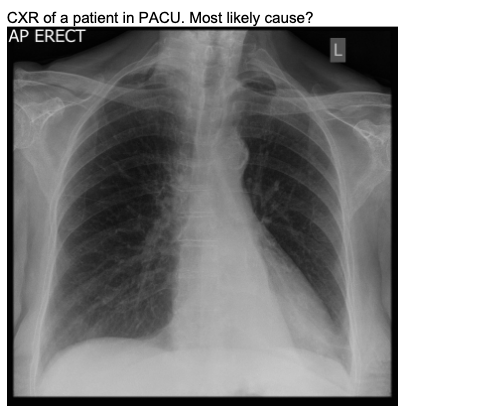

20.1 A 45-year-old man has poor oxygenation in the post anaesthesia care unit after a low anterior resection. His chest x-ray is below. The most likely diagnosis is

a) Left pneumothorax

b) Right pneumothorax

c) Left lower lobe collapse

d) Right lower lobe collapse

e) Normal XR

A

repeat